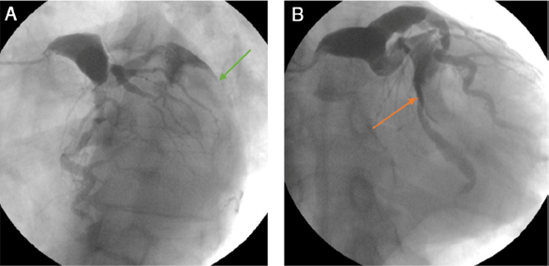

Paciente se sexo masculino, de 62 años de edad, con antecedente de hipertensión arterial, quien ingresó por un infarto agudo al miocardio sin elevación del segmento ST, de 36 horas de evolución, Killip I, sin angina postinfarto. El electrocardiograma mostró una alteración en la repolarización del segmento ST en la pared ínfero lateral. En angiografía coronaria se observó: tronco: ectasia con diámetro de 22 mm (fig. 1A); arteria descendente anterior: tipo III, ectasia en su tercio proximal y medio (diámetro de 20 mm), vaso distal con mínimas irregularidades y flujo lento, TFC TIMI conteo de 61; arteria circunfleja: ectasia severa en su tercio medio y primera marginal (diámetro 30 mm) y evidencia de un gran trombo intraluminal. Vaso distal sin lesiones (fig. 1B); coronaria derecha: vaso dominante, ectasia en todo su trayecto (diámetro de 18 mm) y presencia de flujo lento con TIMI conteo TFC de 59.

Figura 1 A Gran trombo en la arteria circunfleja (flecha verde) y adicionalmente gran ectasia del tronco coronario. B. Ectasia de la arteria coronaria izquierda y gran trombo en la arteria circunfleja (flecha naranja).